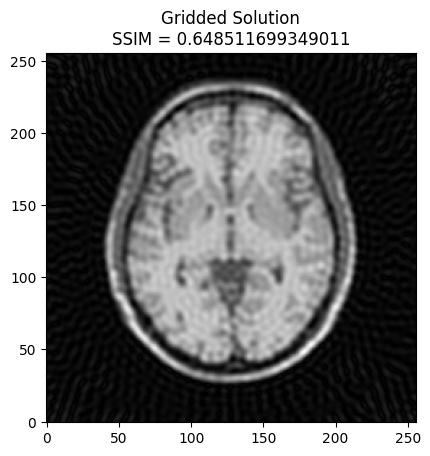

plt.imshow(np.abs(image2), cmap='gray')

# Calculate SSIM

base_ssim = ssim(image2, mri_img)

plt.title('Gridded Solution\nSSIM = ' + str(base_ssim))